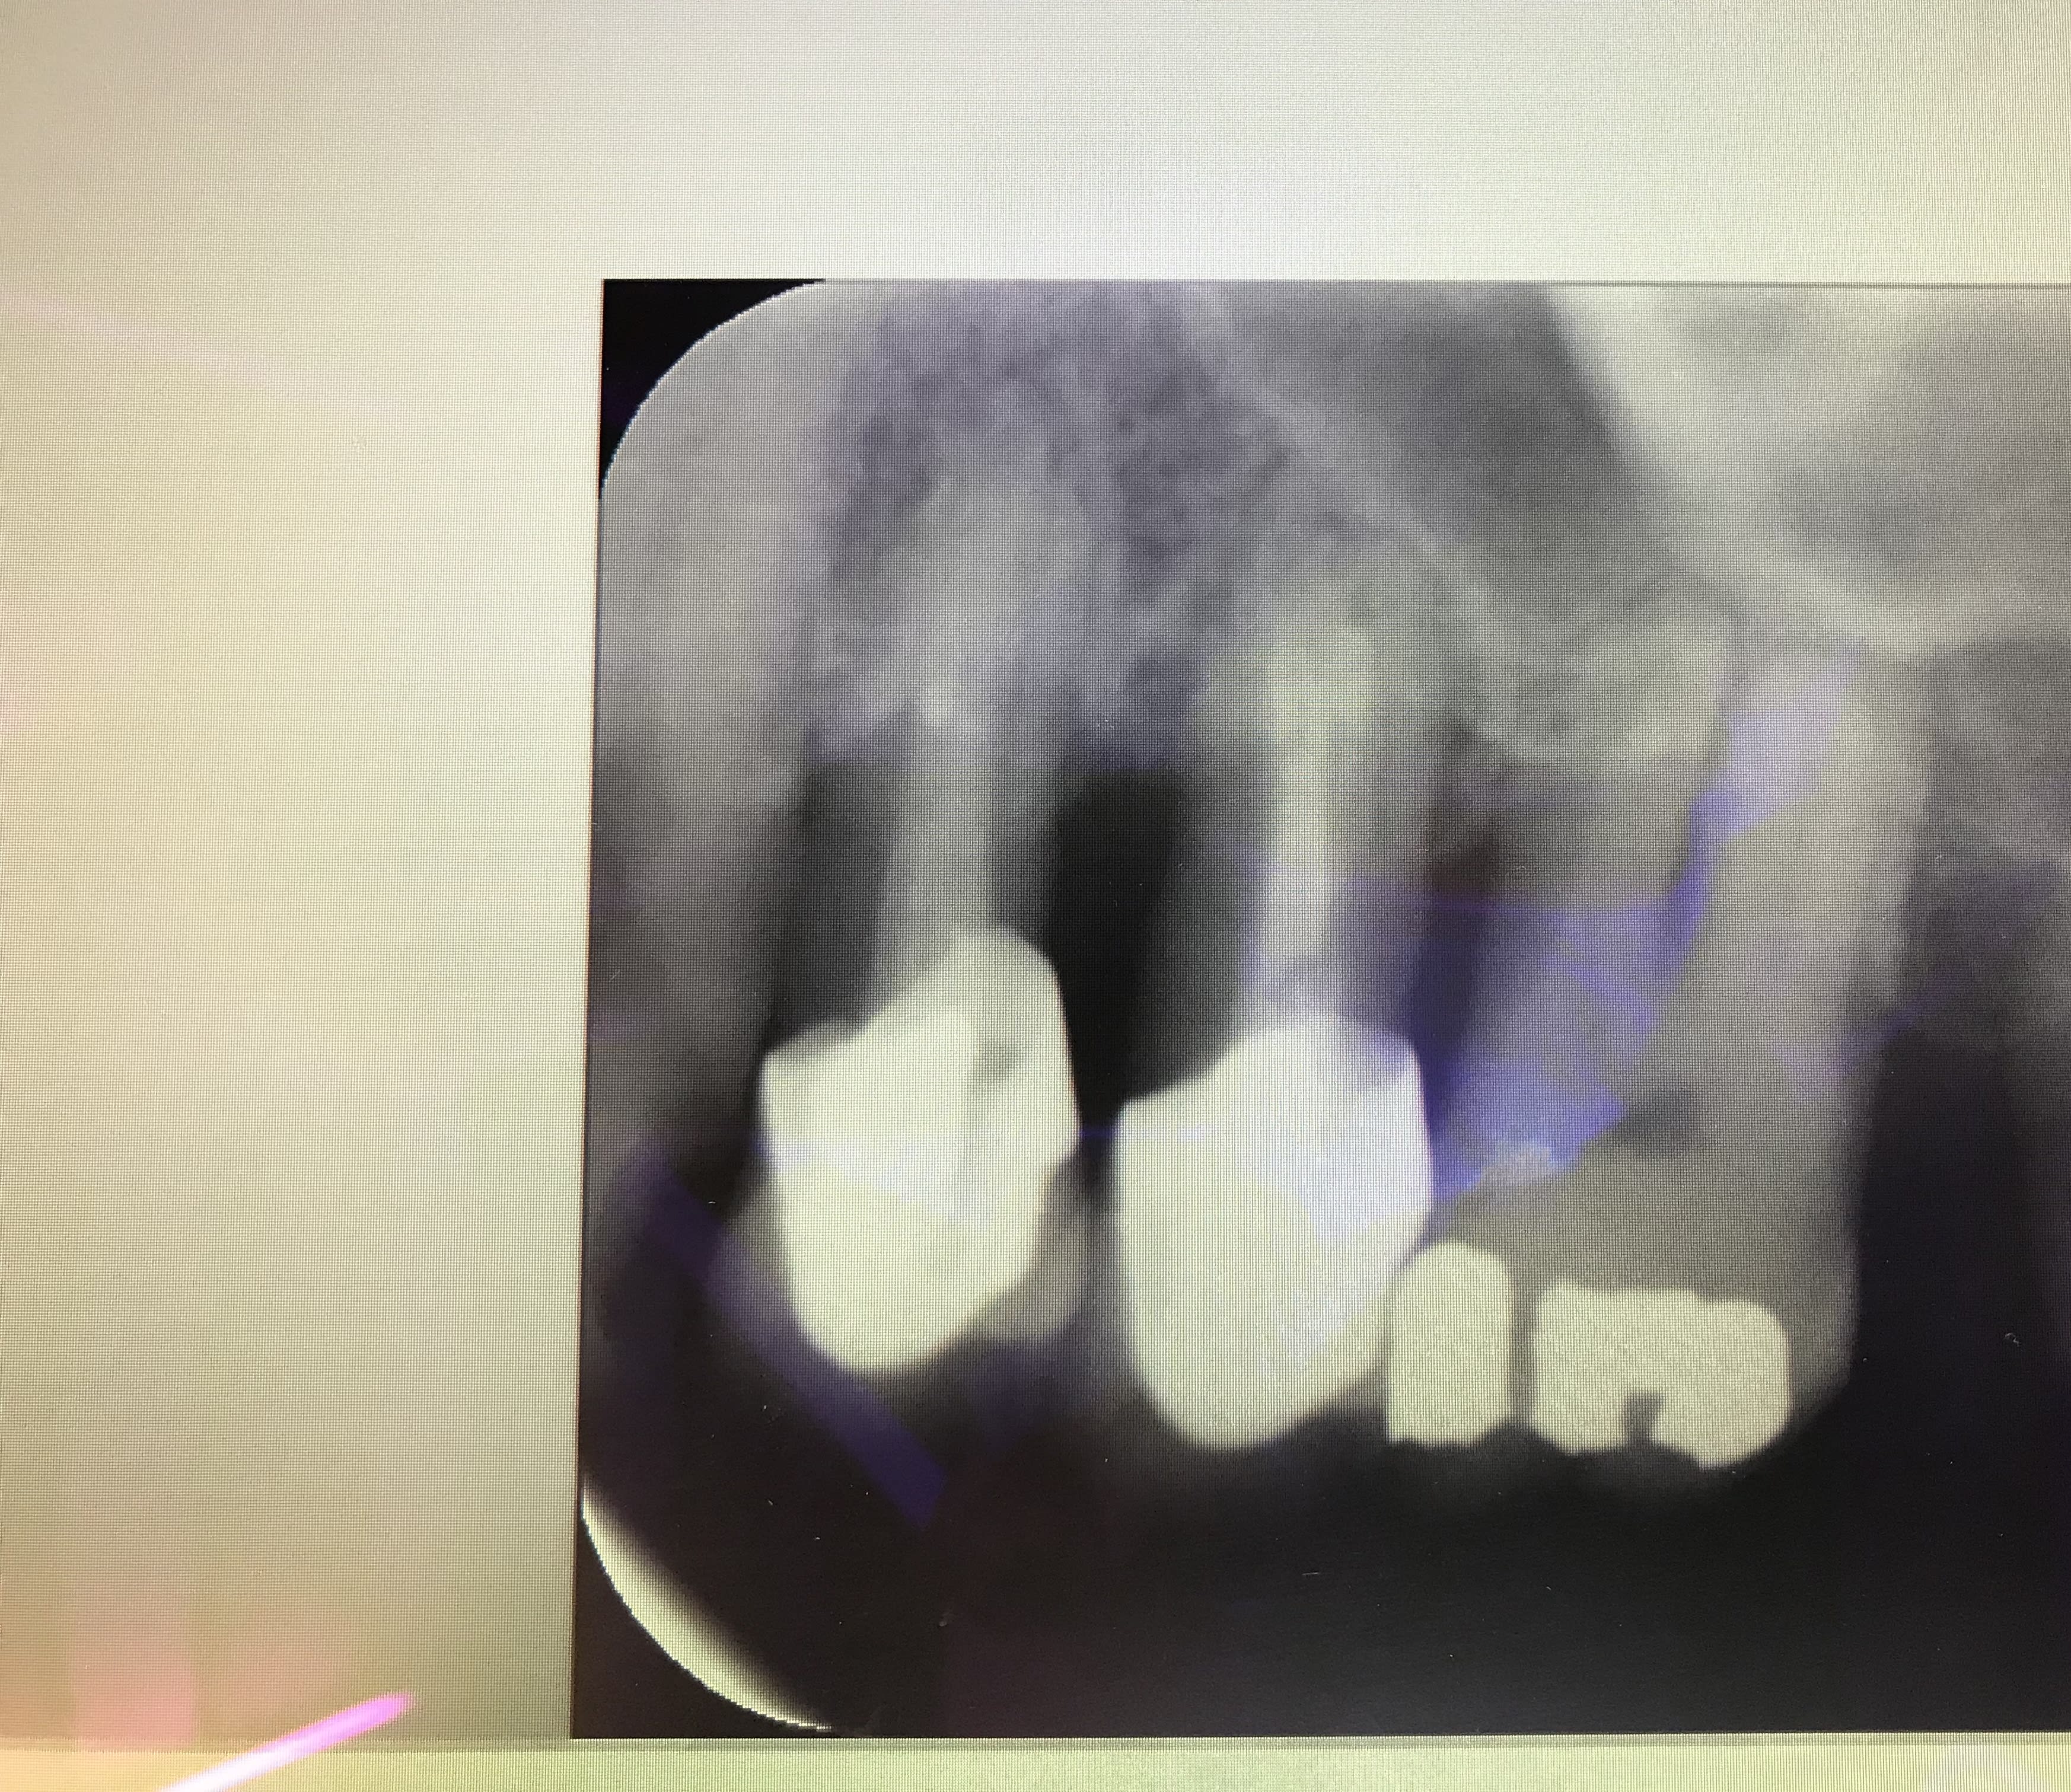

Allez op 1 semaine après la dent est immobile alors qu’elle bougeait dans tous les sens y a 1 semaine. Chir d’aujourd’hui et radio . J’en ai profité pour corriger l’occluSion sur la 5 et 4.

Dents qui sont absolument conservables

C'était combien les profondeurs de poches sur 24 et 25?

Un cliché pré-op?

Mais tu sais quoi la cause de la douleur et de la mobilité c’etait tout simplement un problème d’occluSion sur un terrain paro mauvais. Là la 5 bougeait encore . Normal je n’avais pas touché à sa face occlusale. Je parie que dans une semaine tout sera quasi immobile vu que j’ai retouché à la 5 et à la 4.

Je vais peut être recréer un point de contact 6-5 en créant une cavité sur la 6 et en l’obturant. Car pour l’instant y a un bon petit espace entre 6 et 5. Je sais pas si finalement je vais tout solidariser.